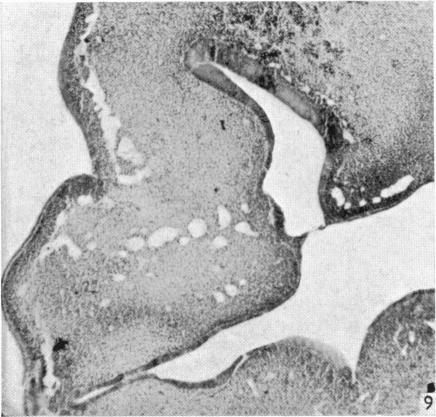

The early development of the nasal cavity and upper lip in the human embryo.

J Anat. 1960 Jul;94(Pt 3):351-62.